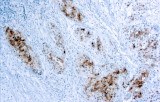

Primary antibodies for immunohistochemistry (IHC) with CE/IVD marking are essential reagents in diagnostic and research pathology, enabling the specific detection of target antigens in formalin-fixed paraffin-embedded (FFPE) tissue sections.

IHC using CE/IVD primary antibodies is a cornerstone in the characterization of gastrointestinal tumors. These antibodies assist pathologists in distinguishing epithelial from mesenchymal origins, determining tumor subtypes, and identifying primary sites in metastatic disease.

- In gastrointestinal stromal tumors (GISTs), KIT (CD117) expression is reliably detected by IHC, while PDGFRA mutations are evaluated through molecular testing, aiding in targeted therapy decisions.